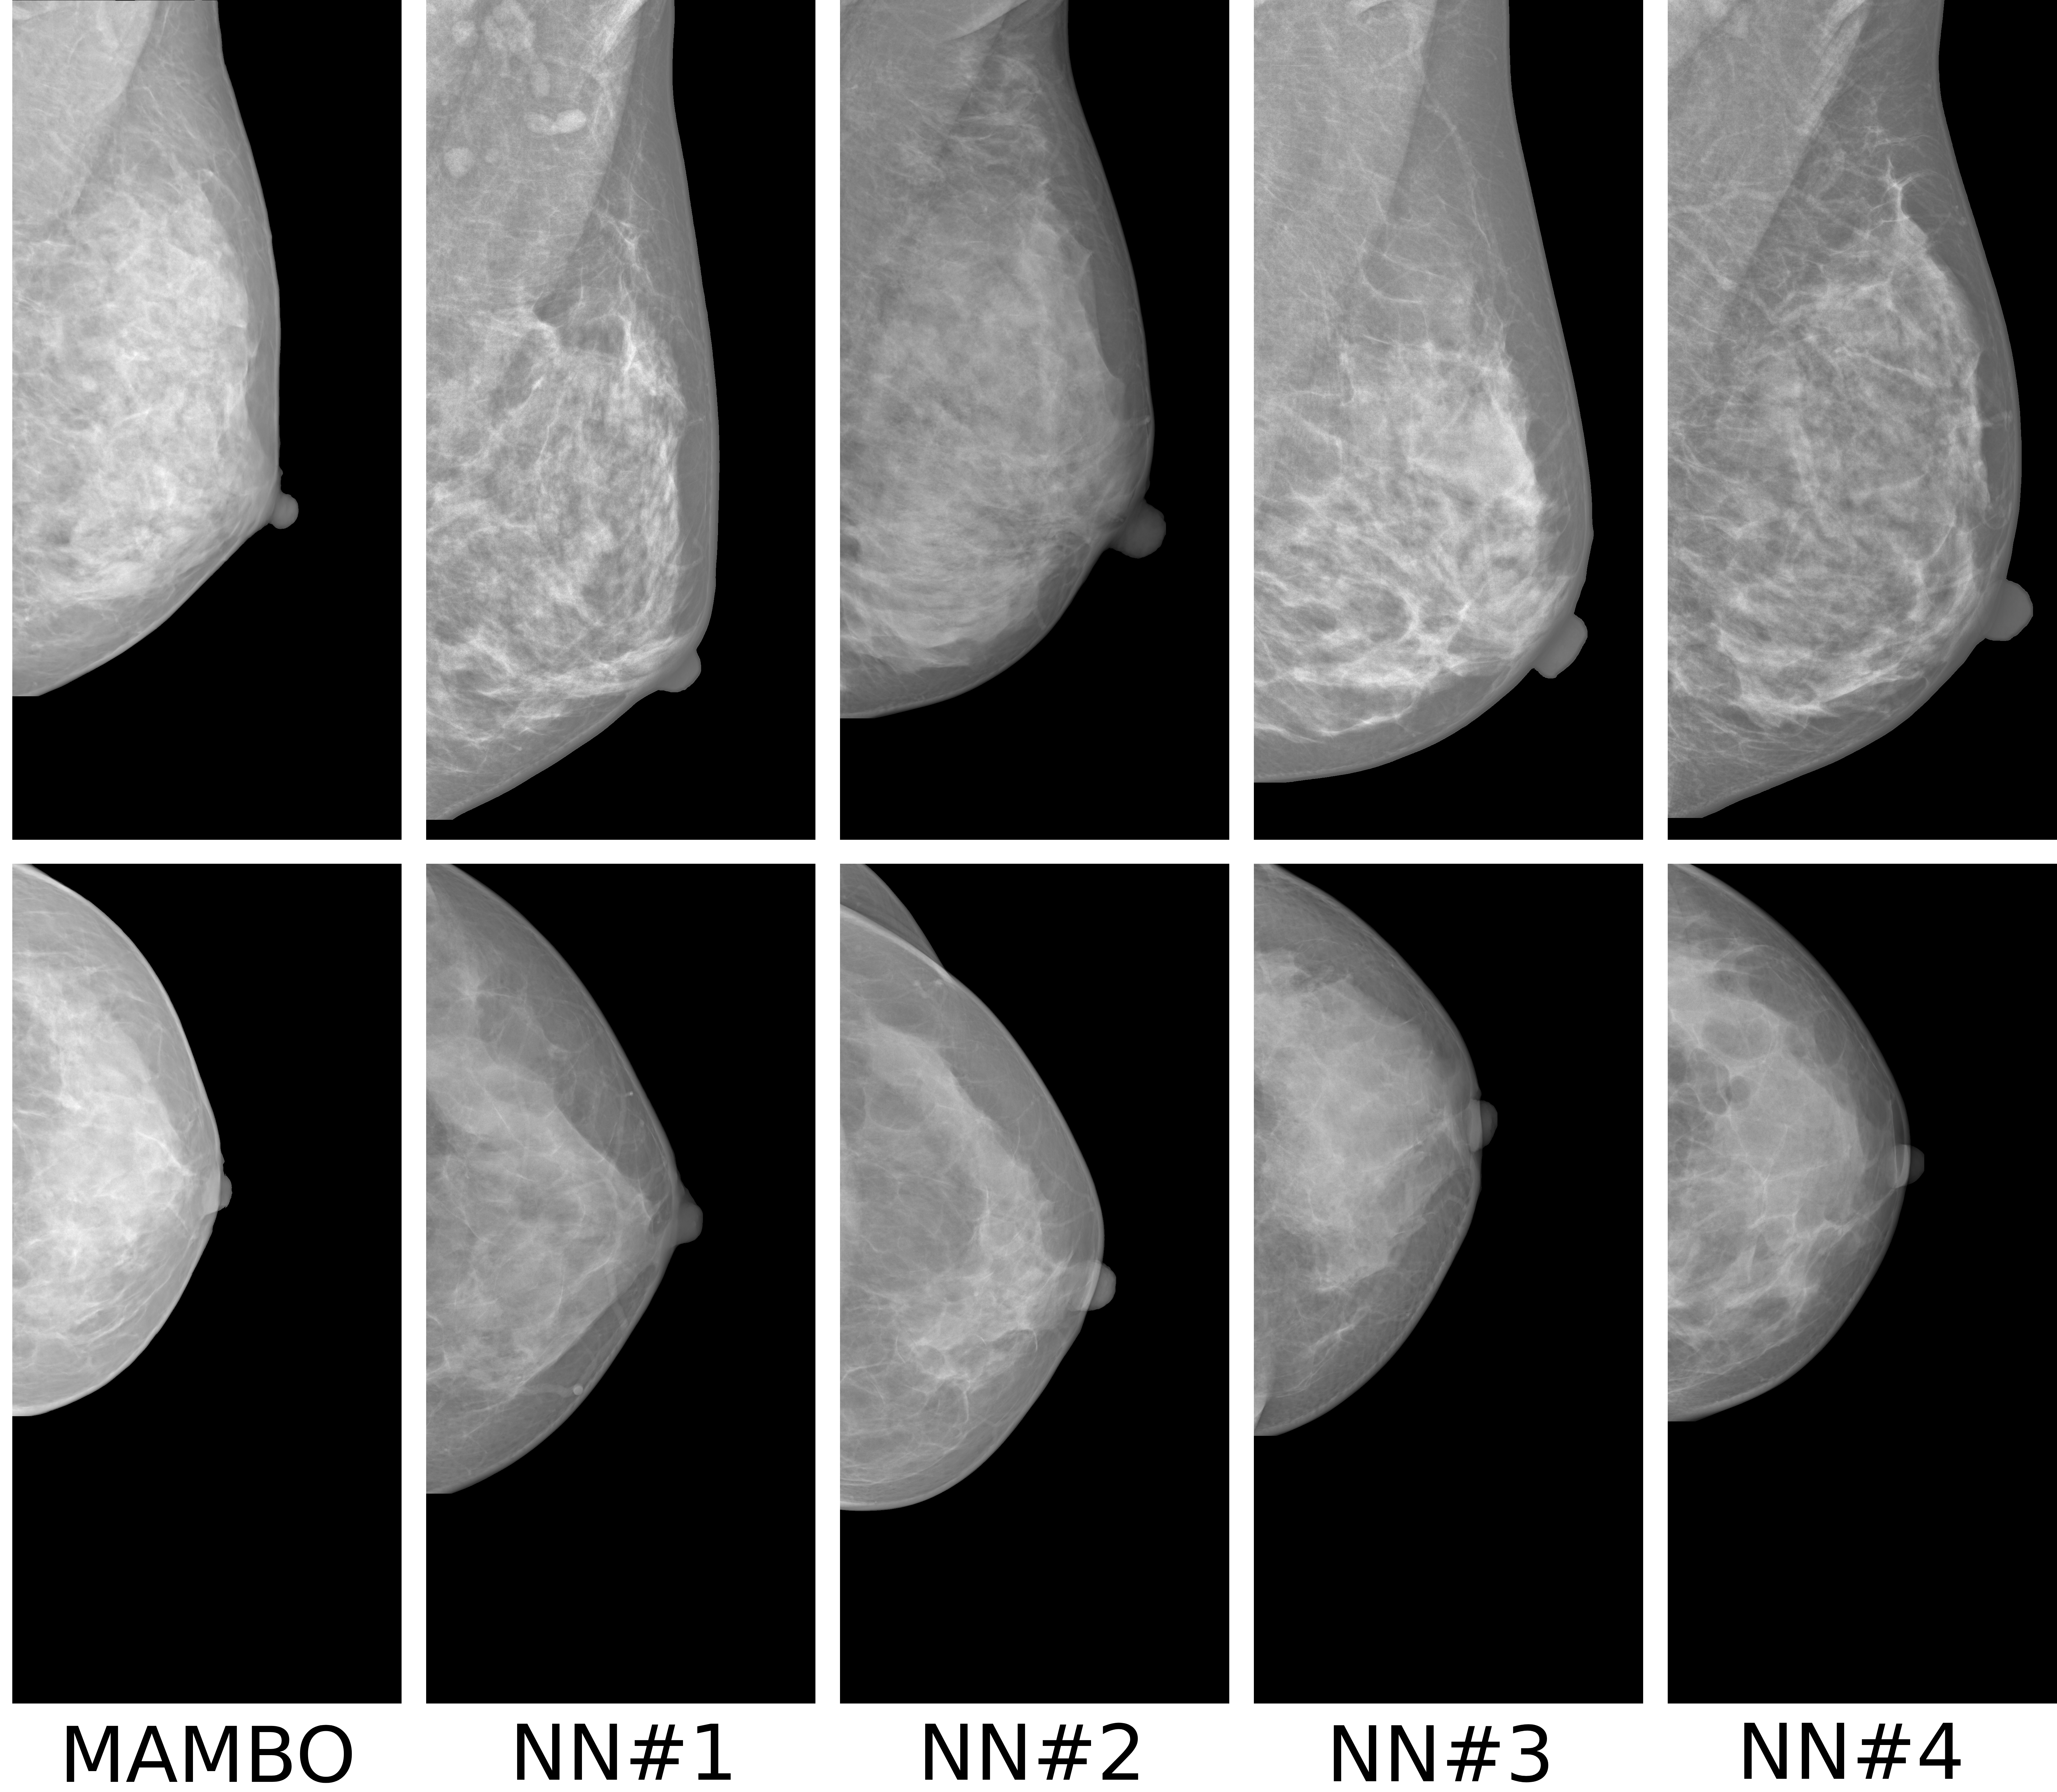

The methodology presented in Patch-DM [4] is closest to the proposed approach. It focuses on synthesizing high-resolution natural images using a patch-based approach and a denoising diffusion model. Unlike MAMBO, which works in pixel space, Patch-DM constructs images by independently denoising patches and composing them in feature space using positional embeddings. Pretrained CLIP [29] is used to obtain initial global context embeddings, which are later optimized during the training. To explore Patch-DM’s potential in the medical domain, we trained it on mammography data to generate images using its original settings with a patch size of pixels, and we use Mammo-CLIP [8] as a pretrained model for obtaining the initial image embeddings. The model was trained for more than two weeks on two NVIDIA A100 GPUs, during which it was exposed to more than 15.5 million mammography images. Despite this extensive training, Patch-DM still struggles to reproduce globally coherent and anatomically realistic mammograms, as shown in Fig. 3(e). This highlights both the limitations of the model in capturing domain-specific structure and its substantial computational demands.

4.1.3 Qualitative Results

The baseline for this task is a single-channel U-Net-based DDPM trained on full-resolution -pixel patches extracted from mammograms. This model learns patch characteristics but performs poorly in image reconstruction tasks. Even if the patch is not generated from pure noise but from the partially noisy patch of an original image, the reconstruction is poor, as shown in Fig. 3(c).

What MAMBO can achieve in terms of qualitative results is presented in Fig. 1 and Fig. 3(d). MAMBO is able to generate high-quality images that are visually indistinguishable from the originals, representing plausible mammogram data to layman eyes. Results are also validated with expert radiologists, with quantitative results shown in Sec. 4.2.

Fig. 3(d) illustrates what MAMBO can achieve in terms of whole mammogram generation. When using global and local context data extracted from an original image, the denoised image (Fig. 3(b)) is difficult to distinguish from the original (shown in Fig. 3(a)). When providing only the original global context and generating local context and target patches from noise, we still observe good results, as we show in Fig. 3(d).